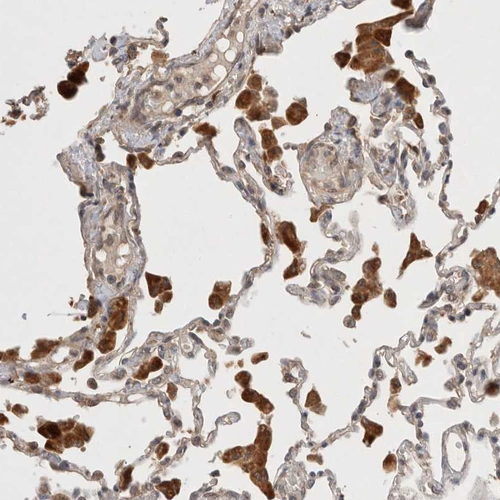

Immunohistochemical staining of human testis shows moderate cytoplasmic positivity in cells in seminiferous ducts.